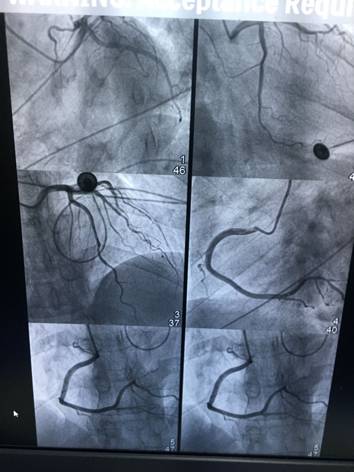

2019年1月23日,市中医院成功为4位患者进行了冠状动脉造影,同时为2名冠状动脉狭窄的患者进行了支架植入。支架植入和冠状动脉造影,是目前诊断、治疗心脏疾病最有效的手段,综合介入治疗中心先进的设备和精湛的技术,为人民群众看病就医带来极大方便,标志着市中医院心血管疾病诊治迈上新的台阶。

心脏介入治疗是一种新型诊断与治疗心血管疾病技术,无需开胸,在影像学方法的引导下,经过穿刺体表血管,借助某些器械,将导管送到病变部位,通过特定的心脏导管操作技术对心脏病进行确诊和治疗的诊治方法,它是目前较为先进的心脏病诊治方法,包括冠状动脉造影术、 PTCA +支架术、二尖瓣球囊扩张术、射频消融术、起搏器植入术、先天性心脏病介入治疗、冠状动脉腔内溶栓术等。